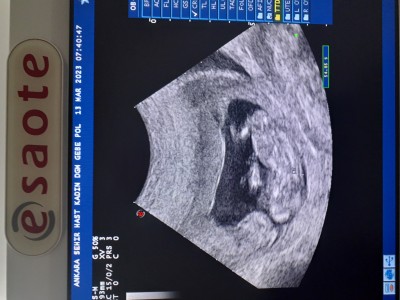

Merhaba beta Hcg değerim haftama göre yüksek çıktığı için ikiz gebelikten şüphelendi bir doktorum 12. Haftadayım sizce bu haftadan sonra böyle bir ihtimal olabilir mi?

Gebelik haftası 12+3